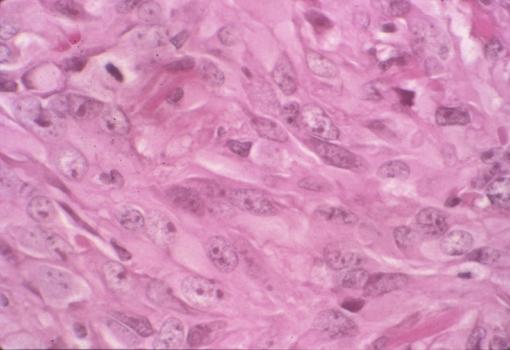

3年3ヶ月間に約2.5倍増大した胃の平滑筋肉腫(66才,男)の病理組織像(ミクロ)  腫瘍の強拡大像です。腫瘍細胞は卵円形から紡錐形を呈しており、核はやや腫大しています。また細胞密度が高く、核分裂像も散見されます。平滑筋肉腫に合致する所見です。

疾患(病理主体)の分類悪性非上皮性腫瘍/平滑筋肉腫(含GIST)

部位(臓器別)胃(部位)/体部

検査方法ミクロ

病変の最大径(ミリ)20〜24

腫瘍の深達度mp